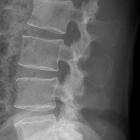

Hemilaminektomie Quelle: eigene Aufnahme Autor: User:Scuba-limp

Röntgenbild

der LWS nach Hemilaminektomie LWK 5 links. Der Dornfortsatz ist erhalten.